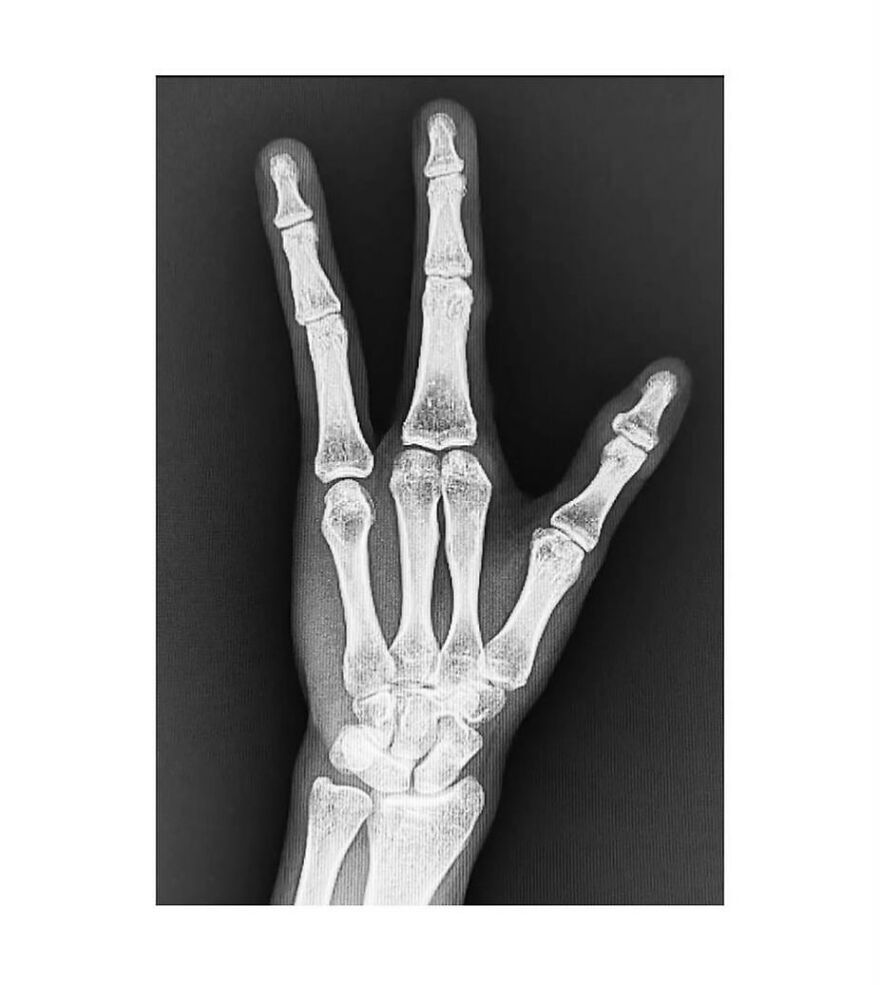

Plain radiograph of wrist joint shows polydactyly with duplication of ulna, duplication of ulnar side of carpal bones, metacarpals and phalanges, absence of radius and absence of thumb. Eight triphalangeal digits are seen. The middle phalanx of medial index finger is hypoplastic